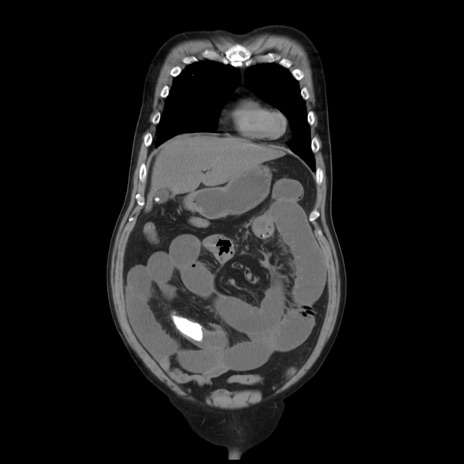

症例20(冠状断像)

【症例】 60歳代男性

【主訴】 腹部膨満、嘔吐

【現病歴】5日前頃より倦怠感を認め食事量減少し4日前の朝嘔吐、食事摂取困難となった。 3日前近医受診し点滴施行され整腸剤などを処方された。 当日他院を受診し、腹部膨満著明、炎症反応の上昇(CRP10.8、WBC11200)あり、紹介受診となる。

【身体所見】 意識JCS1 受け答えがはっきりしないBP 111/57mHg、 P 67bpm、、BT35.2°C、SpO2 97%(RA)、 腹部:膨隆、打診で鼓音あり、全体的に圧痛有り、腸蠕動音(-)、反跳痛ははっきりせず。

【データ】WBC 11400、CRP 14.20

横断像